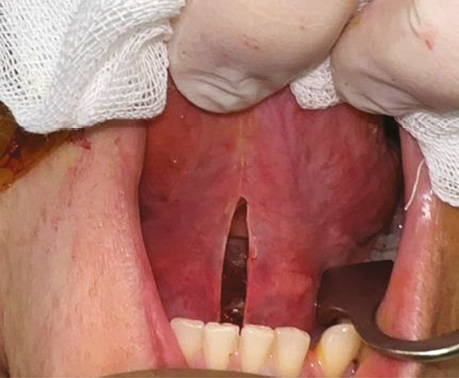

Клінічний випадок № 2

Пацієнт С., 56 років. Діагностовано плоскоклітинну карциному передньої піднебінної дужки з поширенням на корінь язика T2N0M0. Проведено трансоральну CO₂-лазерну резекцію бічної стінки ротоглотки та кореня язика доступом через сформоване «вікно» в ділянці дна ротової порожнини. На рис. 3–6 наведено етапи хірургічного втручання.

Рис. 3. Виконано розріз по серединній лінії дна ротової порожнини між під’язиковим мʼясцем у сагітальній площині

Рис. 4. Дисекція в напрямку до підпідборідного простору між черевцями підборідно-язикового та підборідно-під’язикового м’язів через щелепно-під’язиковий м’яз і між передніми черевцями двочеревцевого м’яза. Накладено лігатуру на кінчик язика, язик виведено через сформоване «вікно» дна ротової порожнини, що забезпечило візуалізацію кореня язика в анфас